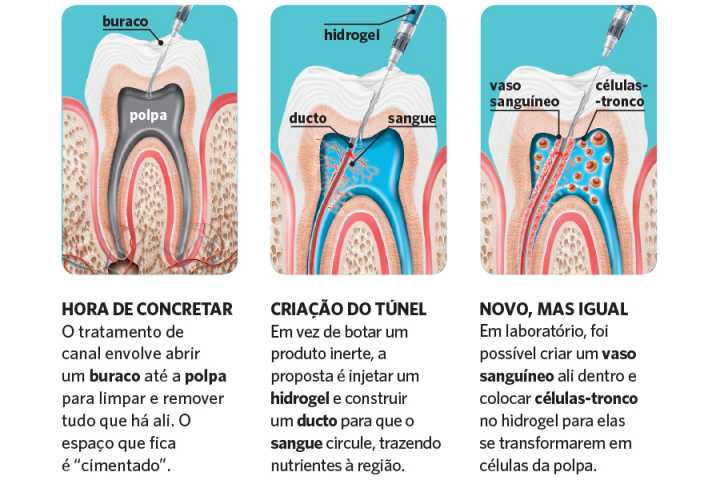

Você quer ver como é o procedimento? A gente te mostra! O tratamento endodôntico, popularmente conhecido como canal, é um processo detalhado para salvar um dente que sofreu danos severos na polpa, aquela parte interna onde ficam os nervos e vasos sanguíneos.

Limpeza e Modelagem Interna: Com o dente anestesiado, o profissional acessa a câmara pulpar. Ferramentas finíssimas, as limas endodônticas, entram em ação para remover todo o tecido inflamado ou infectado. Elas também ajudam a alargar e modelar os canais radiculares, preparando o terreno para a desinfecção.

O Selamento Perfeito: Após a limpeza minuciosa, os canais são preenchidos com um material biocompatível, geralmente a guta-percha. Ela é cimentada para vedar completamente o espaço, impedindo a reentrada de microrganismos. É o fechamento do ciclo de limpeza e proteção.

O Coração do Dente: A polpa dental é o tecido mole no interior do dente, que abriga nervos e vasos sanguíneos. Quando ela é afetada por cáries profundas, traumas ou infecções, o tratamento endodôntico se torna necessário para remover essa parte comprometida.

O Processo de Limpeza: O dentista utiliza instrumentos específicos para limpar e desinfetar os canais radiculares. A remoção do tecido doente e a desinfecção são etapas cruciais para eliminar a infecção e prevenir problemas futuros. É um trabalho minucioso de higienização interna.

Selando o Futuro: Após a limpeza, os canais são preenchidos com um material obturador, como a guta-percha. Esse selamento impede que bactérias voltem a invadir o espaço, garantindo a longevidade do dente. É como fechar a porta para futuras infecções.